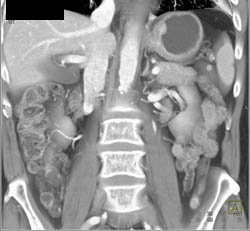

Linitis Plastica